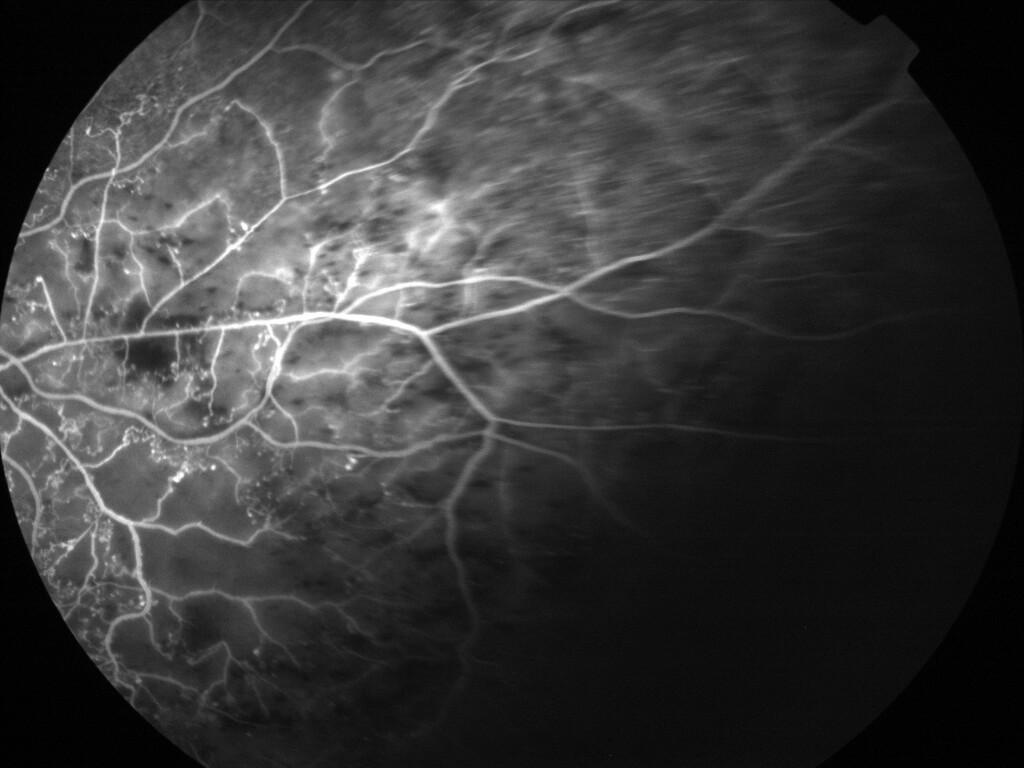

OCCLUSION DE BRANCHE DE LA VTS DE FORME ISCHEMIQUE MAJEURE